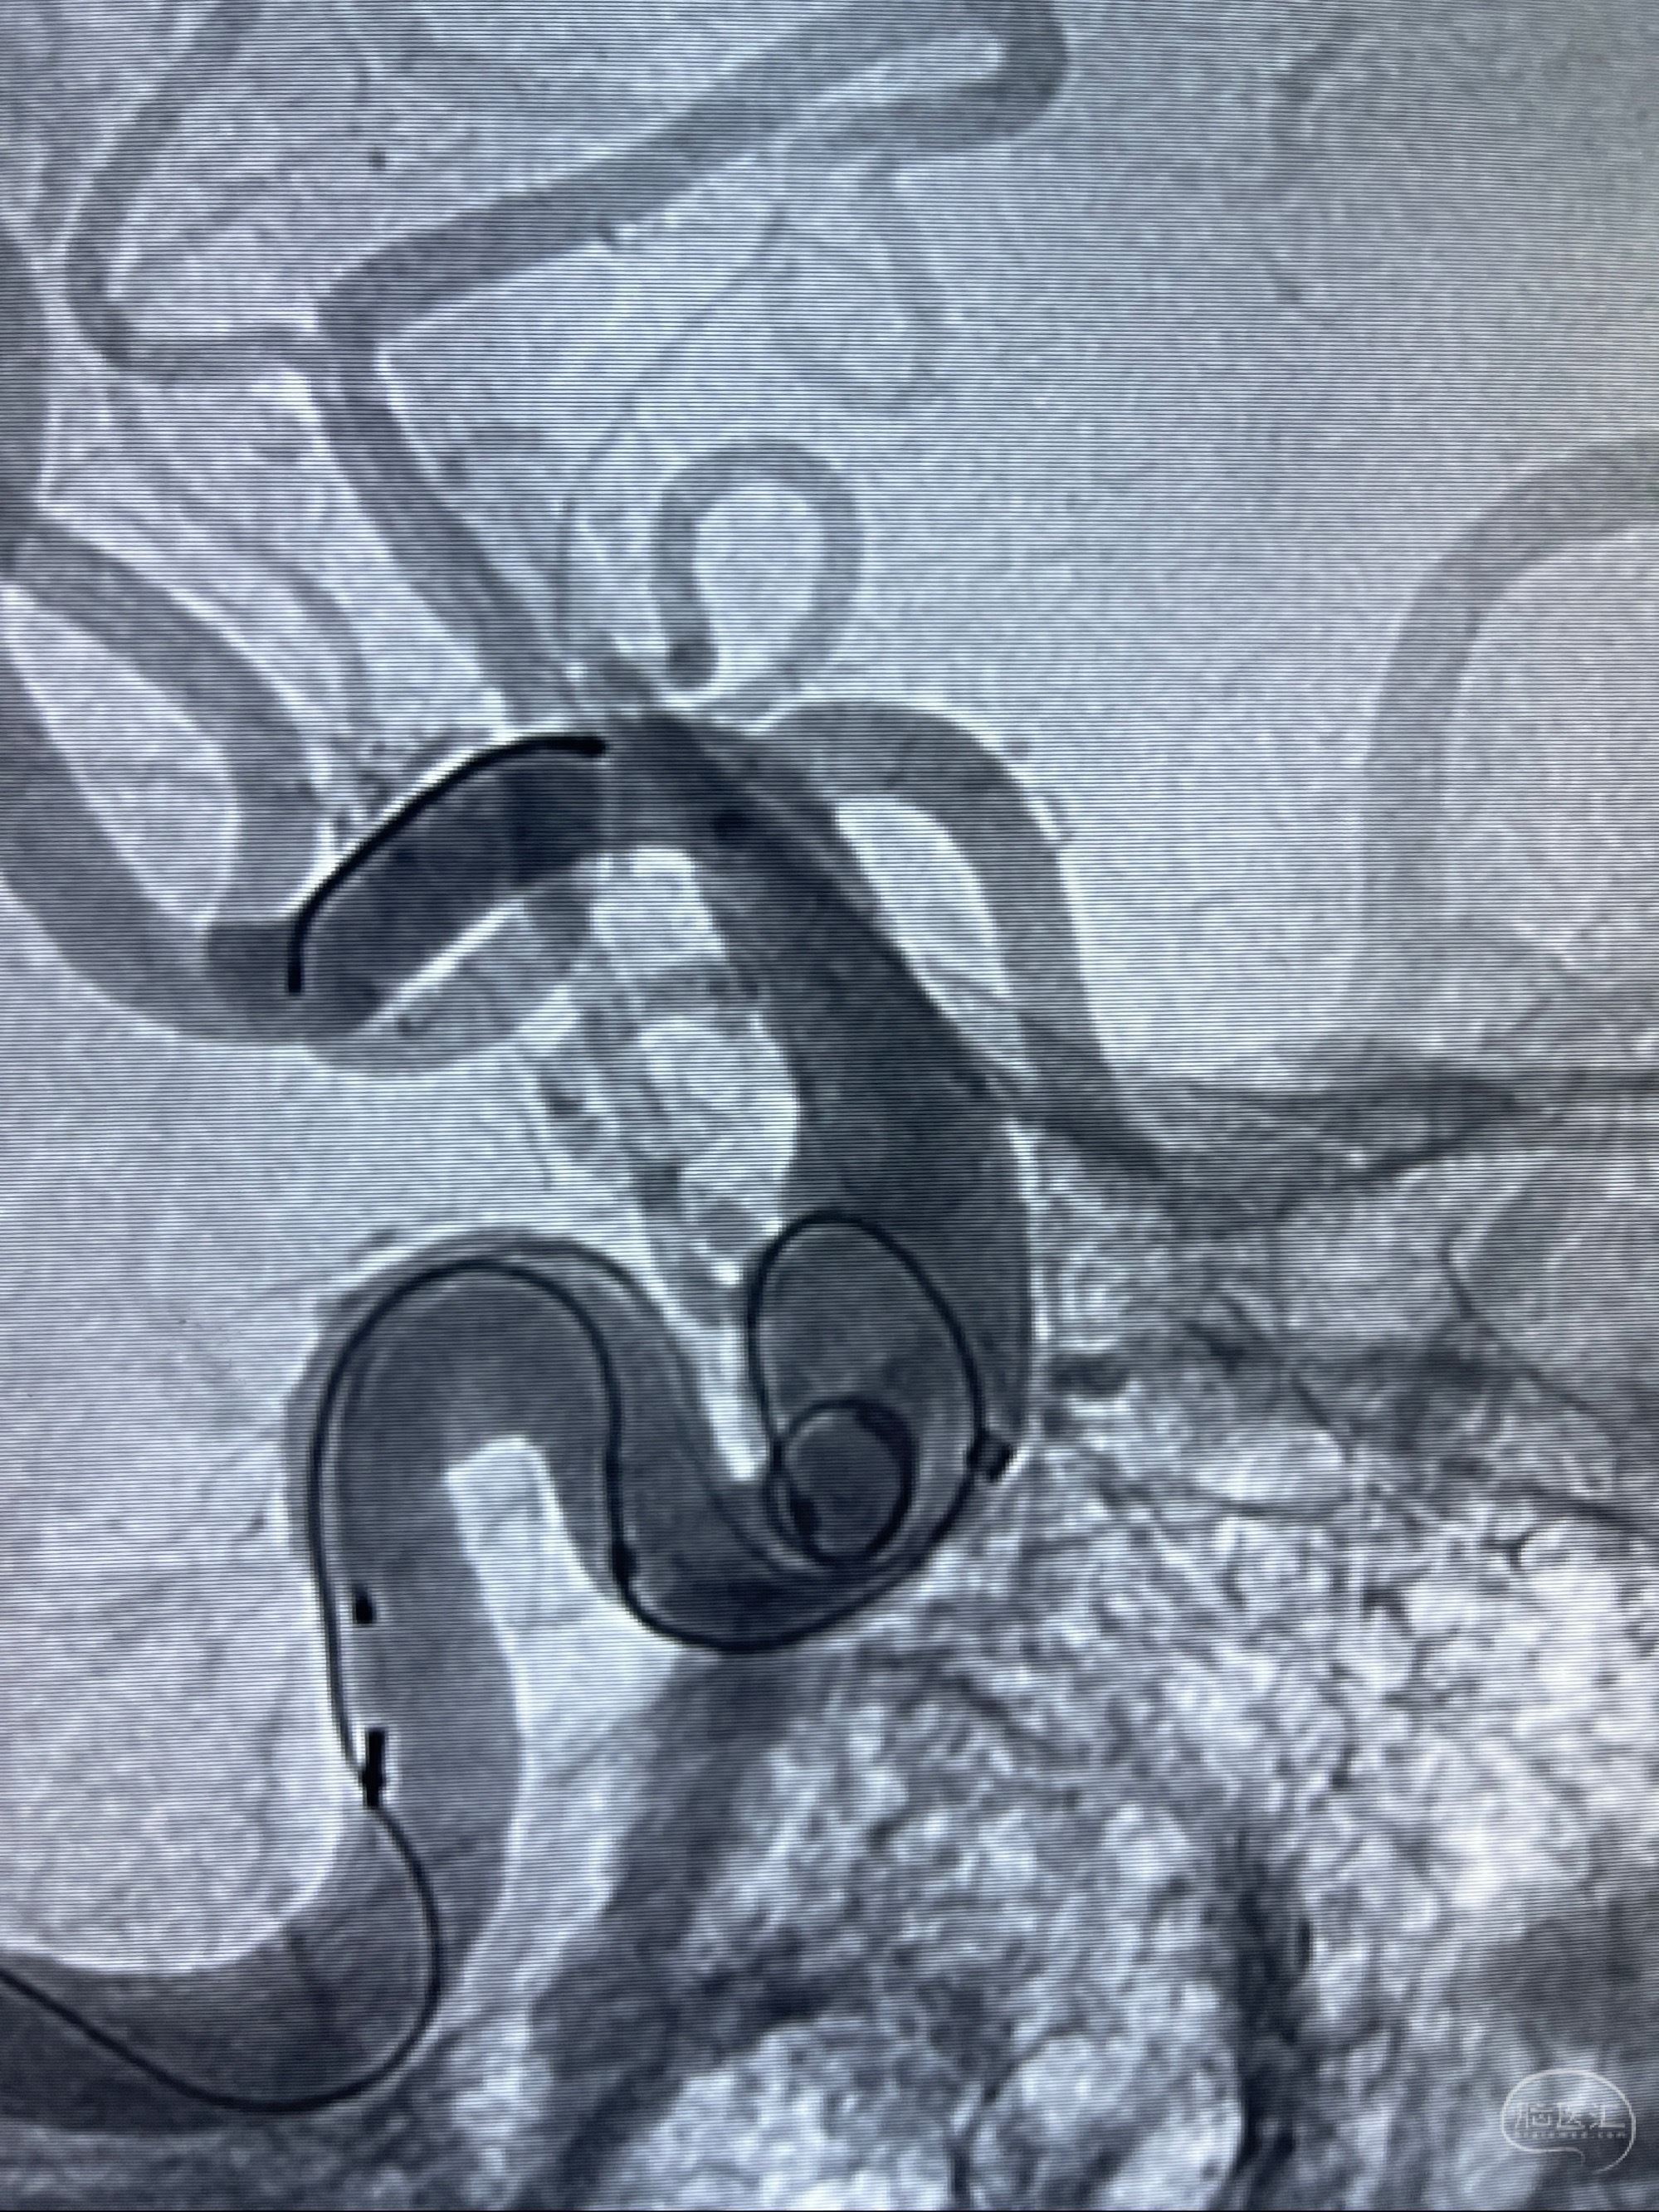

2023-07-27全脑血管造影:双侧颈内动脉眼动脉段动脉瘤,右侧较大

2023-08-01全麻下行双侧颈眼动脉瘤支架辅助栓塞

- pipeling4.5-20mm

- pipeline 4.0-20mm